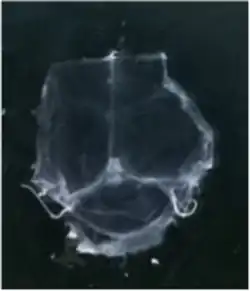

To visualize the dura mater using immunohistochemistry, the dura must first be fixed within the skullcap. It is prepared by cutting around the base of the skull (inferior to the post-tympanic hook) and removing the lower portion of the skull and brain. Following fixation, the dura can be dissected out of the skullcap as a single piece of tissue that can be utilized for histological analysis.[12]

In transgenic mice containing Prox1-GFP or Vegfr3-LacZ reporter genes, the lymphatic vessels may be visualized by fluorescent microscopy or after X-gal staining, respectively.[2]